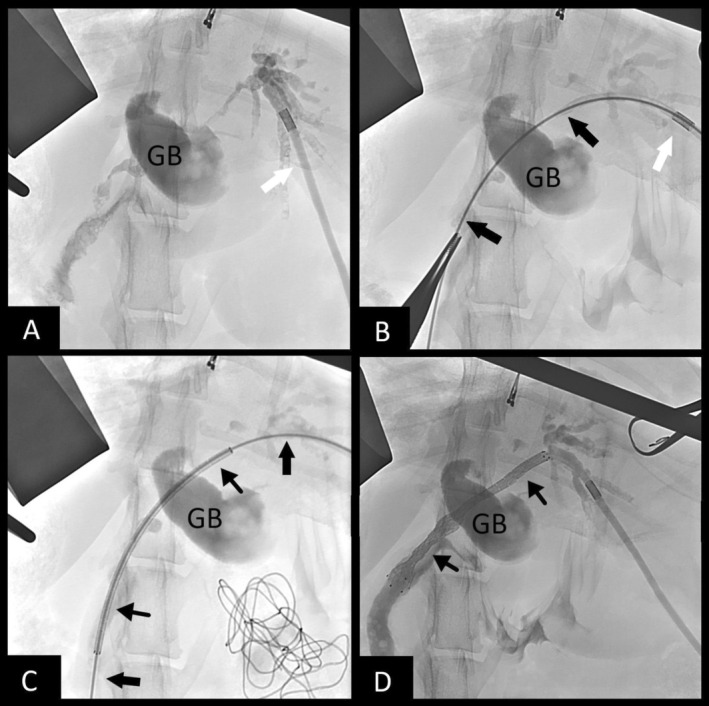

Biliary stenting was recommended and carried out. The patient was pretreated with vitamin K1 (0.5 mg/kg SC q 12 h) and deamino‐D‐arginine vasopressin (DDAVP; 1.0 u/kg SC 15 min before surgery) to minimize bleeding risk. Exploratory laparotomy confirmed biliary obstruction secondary to diffuse tumor burden. Gallbladder puncture using an 18‐Ga IV catheter was performed in an attempt to gain biliary access because the entire CBD was filled with tumor, but was unsuccessful because of occlusion of the cystic duct by tumor. Biliary access then was obtained using intra‐operative ultrasound‐guided puncture of a dilated intrahepatic bile duct of the left lateral lobe using a 22‐Ga IV catheter. An antegrade cholangiogram confirmed obstruction from the intrahepatic ducts at the level of the hilus and throughout the entire CBD (Figure 1A). A 0.018″ hydrophilic guidewire (Weasel Wire, angled 0.018″ by 150 cm, Infiniti Medical, Palo Alto, Cali) was passed through the catheter and into the intrahepatic biliary system. The 22‐Ga catheter was exchanged for a 4 French micropuncture system (Micropuncture Access Set, 4Fr by 10 cm, Cook Medical, Bloomington Ill) and the guidewire was exchanged for a 0.035″ stiffened angle‐tipped hydrophilic guidewire (Weasel Wire, stiff angled 0.035″ by 150 cm, Infiniti Medical, Palo Alto, Cali). Under fluoroscopic guidance the guidewire was navigated through the tumor and CBD (Figure 1B) and into the duodenum. A small puncture was made into the descending duodenum to gain through‐and‐through guidewire access. A 6 mm × 60 mm non‐covered self‐expanding metallic stent (SEMS) then was advanced in a retrograde manner over the guidewire from the duodenum up the CBD and into the left intrahepatic biliary duct (Figure 1C). The stent was deployed across the CBD and into the duodenum (Figure 1D) allowing for decompression of the left side of the liver. A locking loop nephrostomy catheter (Locking Loop Catheter with Stiffening Cannula, 6.5F by 20 cm, Norfolk Vet Products, Skokie Ill) was fed over the guidewire from the liver side and coiled into the left biliary duct for potential future intraparenchymal chemotherapy. A dacron cuff was glued into place on the liver capsule to prevent biliary leakage, and the distal end of the catheter was passed through the body wall using blunt dissection and connected to a SC access port (Medium titanium vascular access port, Norfolk Vet Products, Skokie, Ill) for future access. Total procedure time was 97 min. Bile collected during biliary puncture was submitted for aerobic and anaerobic culture, and all cultures were negative.

Post‐operative radiographs confirmed appropriate placement of the stent and the biliary drainage catheter (Figure 2). Abdominal ultrasonography showed asymmetric biliary tract decompression, with persistent right‐sided intrahepatic biliary tract dilatation (Figure 3A) and resolved left intrahepatic biliary tract dilatation (Figure 3B). The stent was visualized extending from the duodenal lumen through the CBD and into the left lateral liver lobe within the biliary tract (Figure 3C). A large volume of echogenic peritoneal effusion also was observed with hyperechoic mesenteric fat. Fluid analysis was consistent with mild mixed inflammation; no bacteria were seen; aerobic and anaerobic cultures were negative.